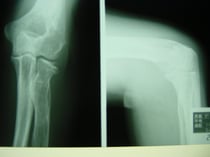

○ 脛骨高原骨折(プラトー骨折)

足を強く地面についた際に体の重みと下から突き上げる力により膝の関節周囲に骨折を起こします。

ちょうど土手が崩れるように折れています。通常は手術によりボルト打ち込み固定しますが、運よく関節面が維持されているので保存的(手術をしない)に治療することができました。

当初は関節内の骨折のため腫れがつよく安静処置が必要です。膝を包むような副子を作り包帯で固定。毎日当院の送迎により来院してもらい、湿布の交換、骨折部位の超音波治療、医療マッサージを施し現在も治療中。